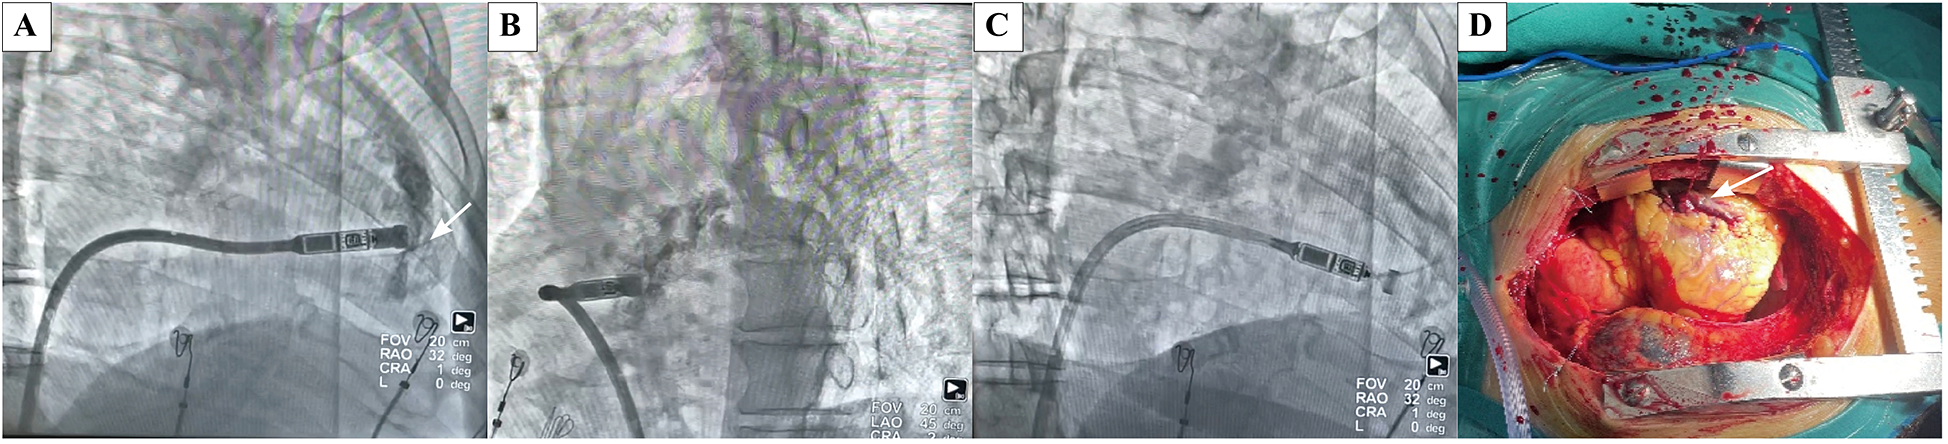

Case 1: An 84-year-old male diagnosed with second-degree AV block (2:1 conduction) and a heart rate of 30–42 bpm for three months was scheduled for Micra VR implantation. The patient had experienced thoracoscopic lobectomy, hypertension, diabetes mellitus, heart failure, COPD, chronic kidney disease (eGFR: 29 ml/min; creatinine: 181 µmol/L), and moderate anemia. Pericardial effusion was detected immediately following the injection of contrast medium, prior to device implantation (Figures 2A,B). LP was implanted at the mid-septum with another deployment. Electrical parameters were optimal (Figure 2C). Emergent pericardial drainage yielded over 800 ml blood, and the blood pressure dropped to 80/60 mmHg. Emergency thoracotomy revealed myocardial perforation at the anterior interventricular sulcus, located between the right ventricular free wall and septum, attributed to trauma by the tip of the delivery catheter (Figure 2D). The patient was transferred to the intensive care unit for three days and was discharged two weeks later without residual complications.

Figure 2

Case of an octogenarian who developed acute cardiac tamponade during the procedure and subsequently underwent emergency open chest surgery. (A) Extravasation of contrast agent into the pericardial space following contrast agent injection in RAO(white arrow indicates the perforation site). (B) Extravasation of contrast agent into the pericardial space following contrast agent injection in LAO. (C) Extravasation of contrast agent into the pericardial space following contrast agent injection in RAO, there are amounts of excess fluid around the heart. (D) Perforation caused by cutting of the delivery catheter was located at the anterior interventricular sulcus, between the right ventricular free wall and septum at open chest surgery. (white arrow indicates the perforation site).

Pericardial effusion occurred early in the operator's learning curve. One octogenarian with cardiac tamponade required emergency open-chest surgery, during which 800 ml of bloody pericardial fluid was drained. The perforation was located at the anterior interventricular sulcus, between the right ventricular free wall and septum, and was attributed to the sharp tip of the delivery catheter. This case underscores the importance of gentle manipulation of the delivery system, especially during traversal of the tricuspid valve, and avoiding forceful advancement toward the target site before contrast injection to prevent cardiac perforation. Implanting LP in the septum rather than the apex may help reduce the risk of cardiac perforation. However, differentiating between septal and anterior interventricular sulcus positioning based solely on contrast radiography can be challenging. A relatively sparse trabecular pattern in the RAO view may indicate placement near the anterior interventricular sulcus. Notably, LP implantation in elderly patients may demand technical expertise due to altered cardiac positioning resulting from scoliosis, prior pulmonary lobectomy, atelectasis, or other thoracic deformities. The incidence of pericardial effusion increases significantly with more deployment attempts (9).